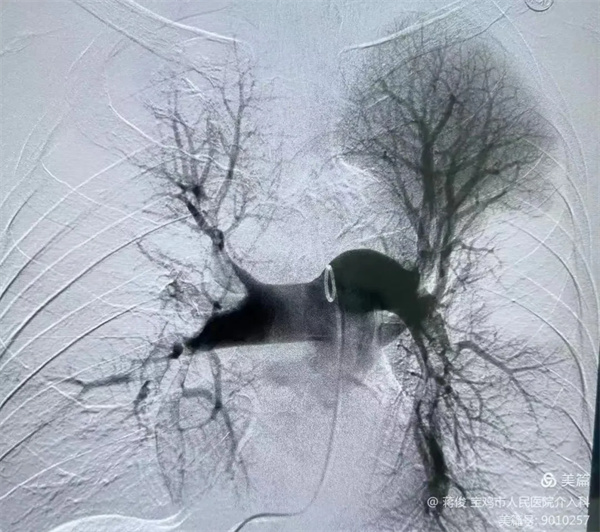

3.webp.jpg

肺動脈DSA造影提示肺動脈主干及分支大量血栓,予以肺動脈造影、血栓溶解、肺動脈碎栓

4.webp.jpg

置入下腔靜脈濾網,預防下肢靜脈血栓再次脫落